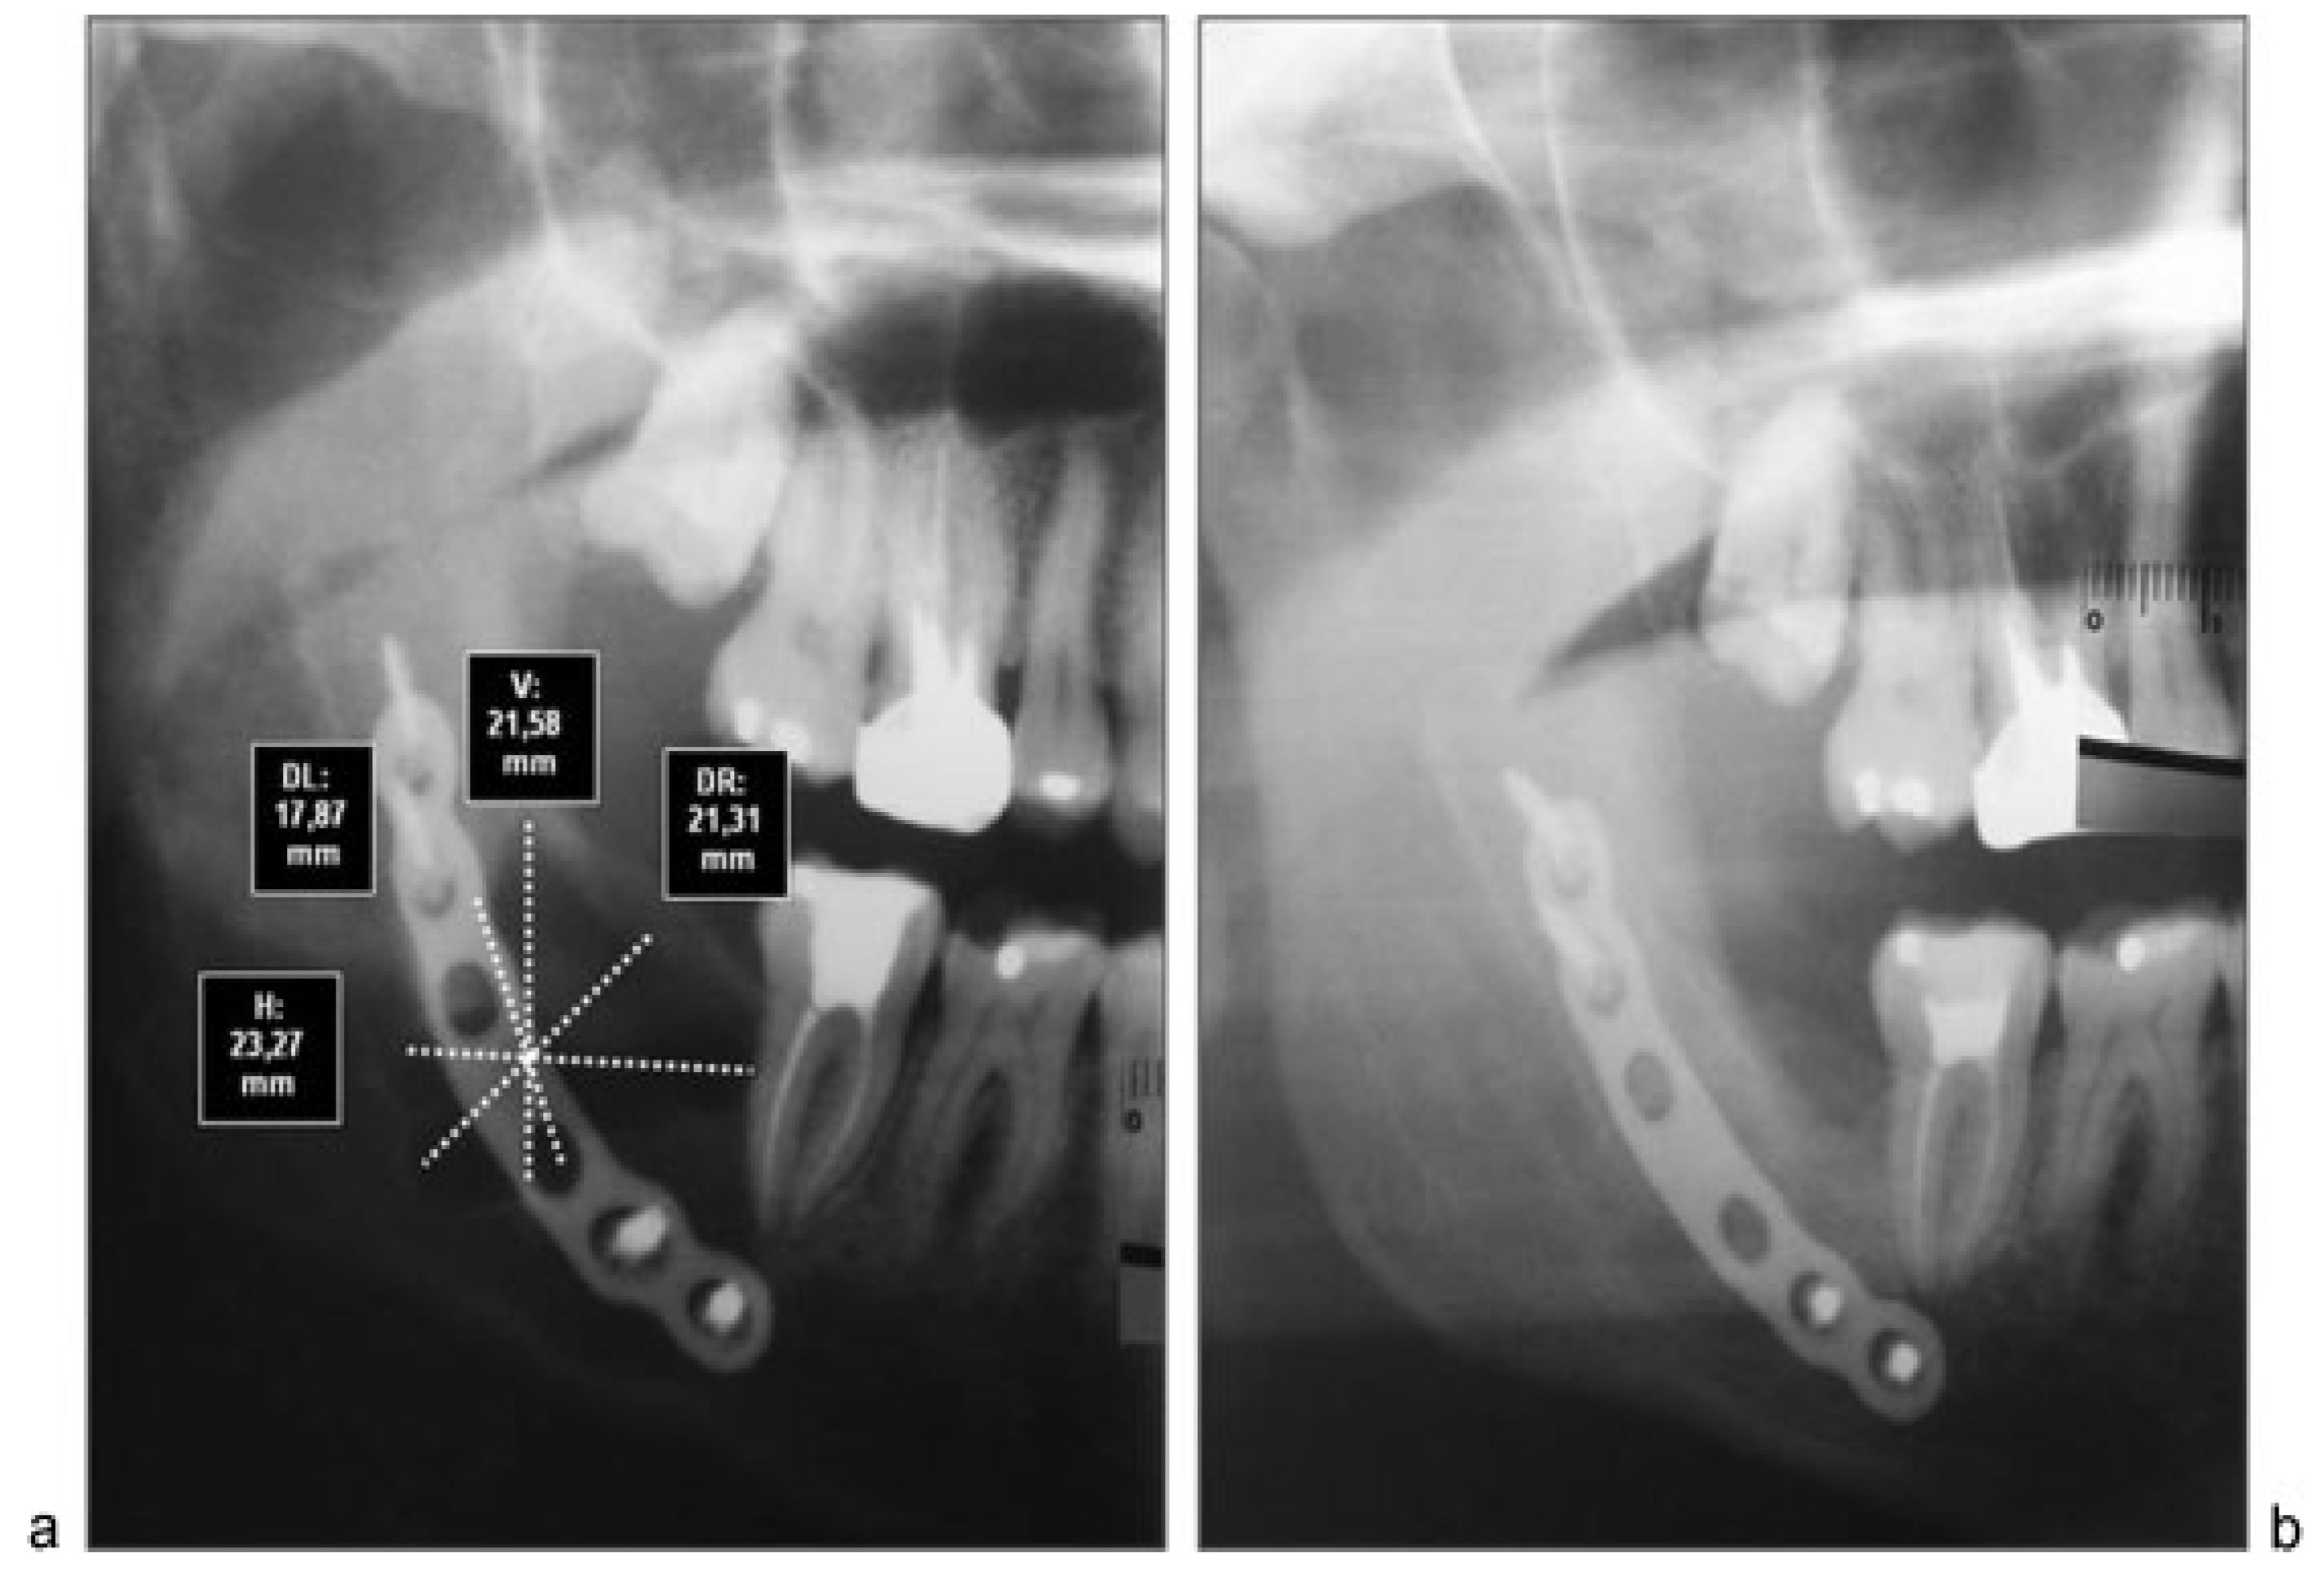

The 18 patients were divided according to age, histopathologic diagnosis, postoperative control time, and percentage of bone regeneration (Table 3). The sample analysis showed an average decrease of 85.59% in the horizontal measures, 89.53% in the vertical, and 88.98 and 89.81% in the left and right diagonal, respectively. The percentage of reduction was greater in diagonal and vertical measures compared with the horizontal measures, with an overall average reduction of 88.47%. Twelve patients (66.6%) had 100% bone regeneration after 6 months of cystic enucleation. In the remaining six patients, bone regeneration was approximately 50.4 to 78.56% with an average of 65.43%. In four cases (patients 2, 11, 14, and 15) one of both bone plates (buccal or lingual) were destroyed by the lesion; therefore, bone regeneration was clearly lower (Table 3 and Table 4).

Although computed tomography provides better information about bone regeneration after surgery, to prevent high radiation dose panoramic radiographs can be considered enough for the purpose of postoperative control, so that we choose this last option (Figure 2a,b, Figure 3a,b and Figure 4a,b).

Figure 4. (a) Preoperative radiograph of patient 11 with linear measures after X-ray calibration with Nemoceph program. (b) Postoperative radiograph 6 months after surgery with postoperative measures of residual cavity.